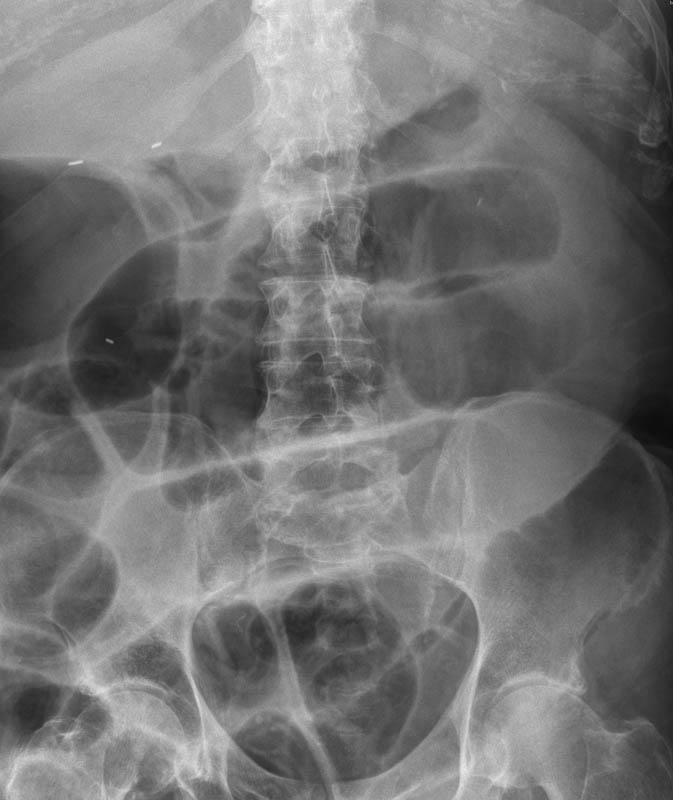

Diverticulosis de colon.

Diverticulosis de colon. Megacolon.